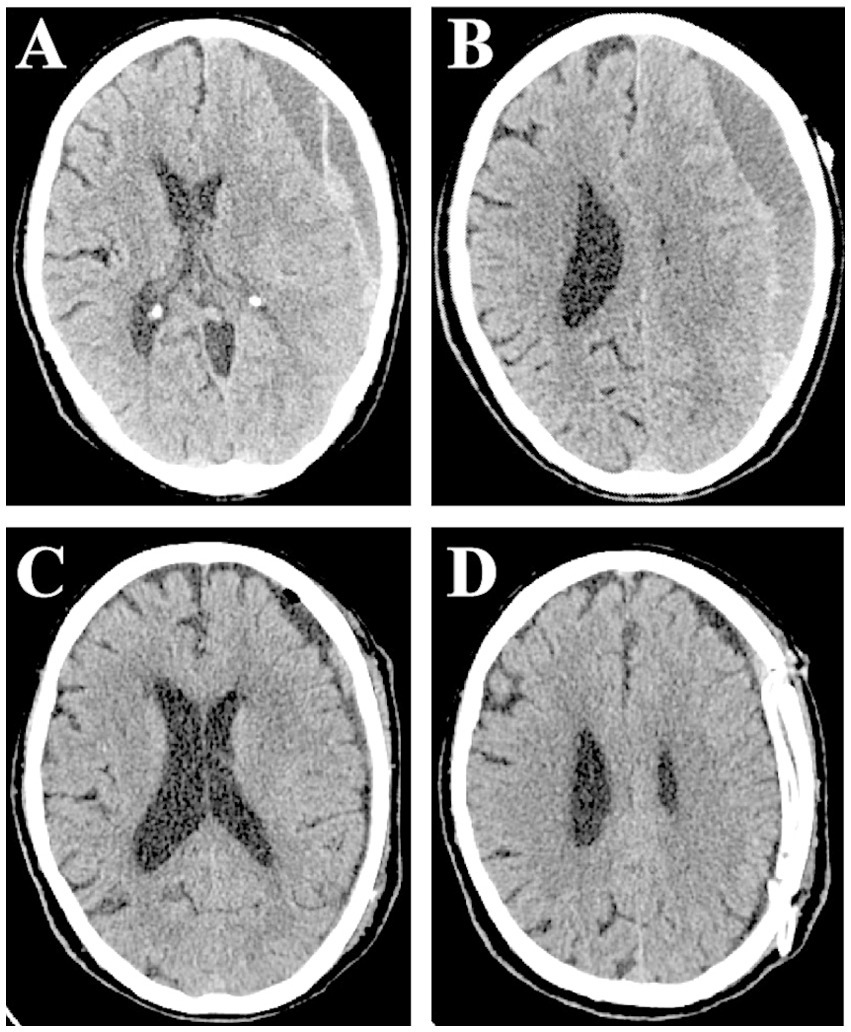

Figure 2

Computed tomography scan showing septated chronic subdural hematoma on the left side. Small red arrows indicate SCSH with two clear compartments (A,B). Early postoperative scan showing significant clearance of hematoma, regression of midline shift, and slight intracranial pneumatosis (C,D).